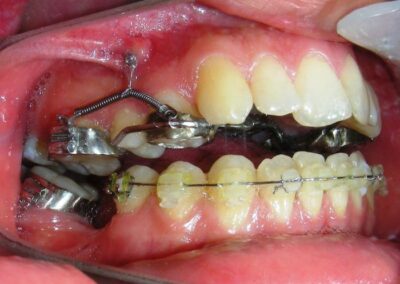

Was installed a Hyrax-type 10mm palatal expander of the Brazilian trademark Morelli® , modified by the author to be adapted to receive TADs microscrews, in order to initiate maxillary disjunction with MARPE (Mini-implant Assisted Rapid Palatal Expansion), TADS was installed with skeletal anchorage placed bilaterally having as references the roots of the maxillary canines and first premolars. Prior to insertion, local infiltrative anesthesia was administered using 2% lidocaine hydrochloride with 1:100,000 epinephrine. A total dose of approximately 0,8 mL per side (cortical infiltration technique). The TADs were inserted under aseptic conditions using a manual driver. Microscrew Evolution 1,6 Ø x 10 mm from the Argentine brand Odontit® . The Hyrax expander was then fitted and activated after 48 hrs .

Protocol of one activation per day was followed for a period of three weeks where the first clinical and radiographic evaluation was performed, showing clear signs of skeletal expansion, including the presence of a midline diastema. One more week of activations was added with a total of 28. The patient reported moderate headache during the first week of activation.

Having successfully achieved the expansion, we proceed to the intrusion of the posterior superior sectors, modifying the Hyrax by adding anchoring hooks at the buccal level of the first premolars. Using the Hyrax as anchorage, we sought a parallel intrusion. This could be replaced by a palatal bar. TADs were installed bilaterally at the mesial level of the first molars, inserting them as parallel as possible to the roots.